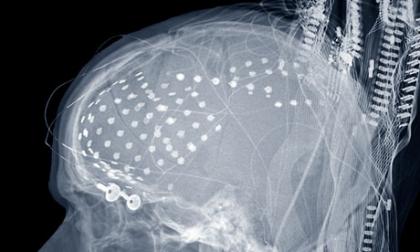

这研究在Frontiers of Neuroscience里出版,他们只能用大脑里已经有电极的人,因为光用脑波读取头盔(读取头皮上的电活动)的话不够铭感到可以分辨字母的讯号(头骨会干扰讯号)。

所以这限制到只有七人能参加(全部都有癫痫症而且已经有治疗用电极植入脑里)。很不幸的是对研究家来说这些电极只有植入在需要重新接线的大脑区域,并不是全区域。